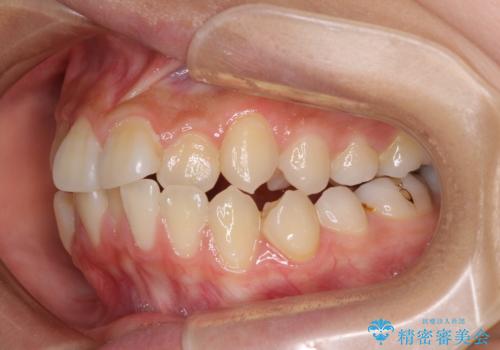

- 下顎の前突感と前歯の叢生を気にして来院された患者様です。

下顎前方位の骨格のため、下顎歯列に対して上顎歯列の幅が狭くなっていました。